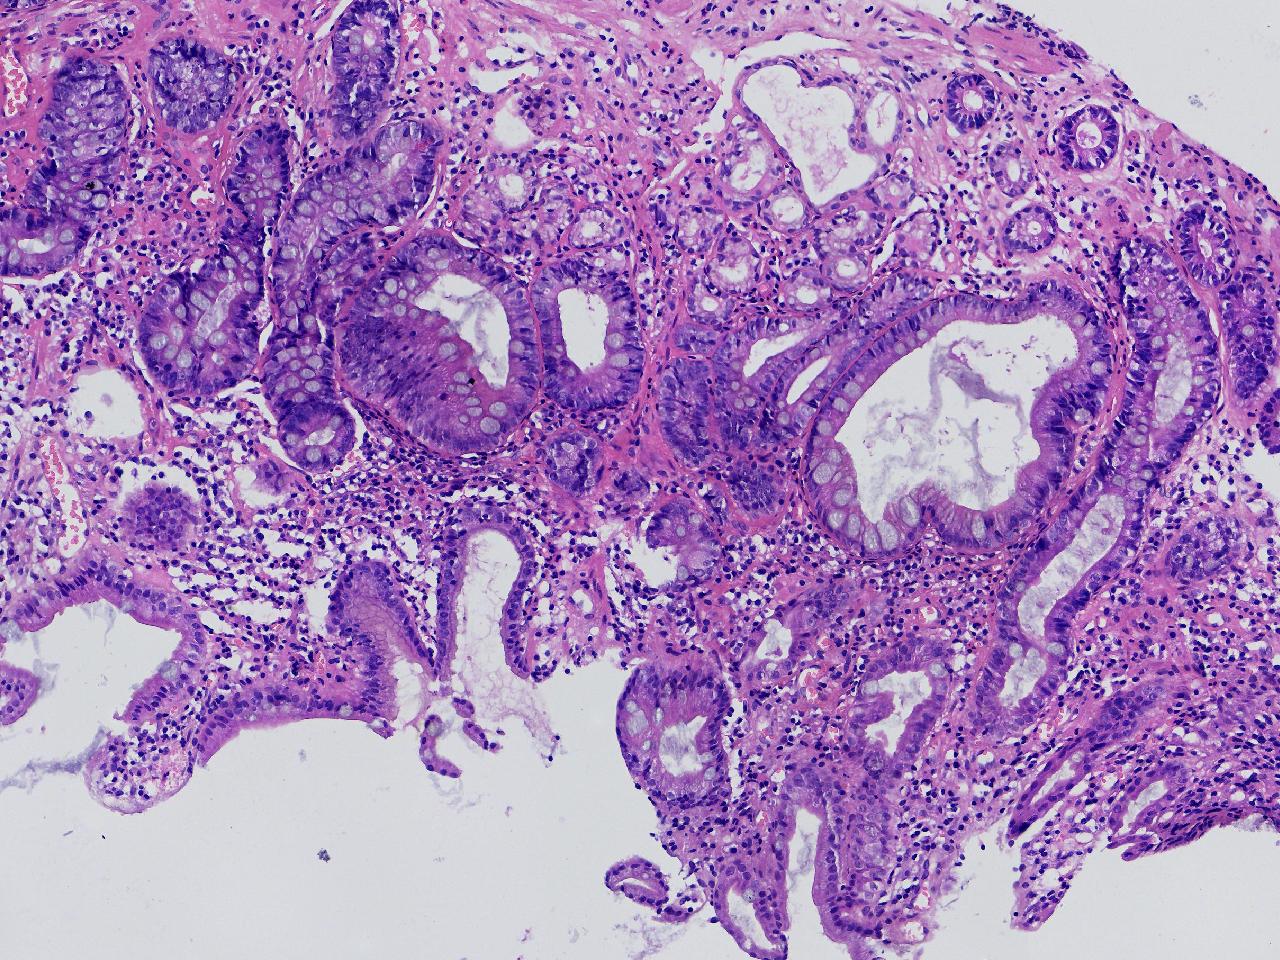

1.间质内淋巴组织有问题吗? 2.有没有低瘤变?

一般病史男,65岁,胃镜活检,胃窦粘膜红白相间,花斑样改变,大弯侧粘膜变薄,血管透见,可见多发片状充血糜烂灶及点状褐色物覆着,活检2块送检,质软弹性可。

标本名称胃窦活检

大体所见灰白色不整形软组织2块,直径均0.2厘米。

慢性萎缩性胃炎伴肠化,固有层淋巴细胞聚集

萎缩性炎,伴有肠化,淋巴组织挤压变形,感觉没有太大的问题。

炎性,无瘤变。